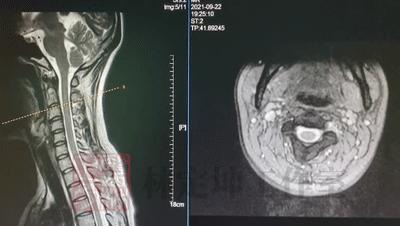

04 核磁共振检查(MRI)

MRI检查,又名核磁共振检查。这项检查能够利用强大的磁场,让身体中所有的水分子震动起来,从而根据震动形成的影像差异来 检查组织是否存在病变 。

可得信息:

(1)检查颈椎椎管内部的神经组织,包括形态特征、是否发生损伤、是否有水肿或者变性的情况;

(2)检查椎间盘是否存在损伤、破裂、突出,导致压迫神经的情况;初步判断感染、结核、肿瘤等病变的可能性。